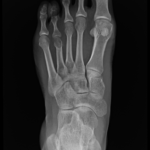

Posttraumatic bone deformities are fractures that heal in a displaced, angulated, rotated, or shortened position.

Fractures can heal in an incorrect position with shortening, angulation or rotation. This is called a malunion.